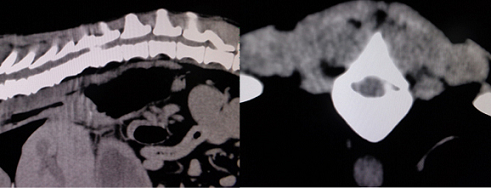

【画像診断】~ダックスフンド、雄10歳、グレート3の椎間板ヘルニア~

▲ダックスフンドのCT像、病変の部位は胸椎T11-12、白い部分(武蔵野動物CTセンターにて)

▲同じく胸椎T11-12、3D画像のCT像、ワークステーションを用いたCTの仮想内視鏡像

はい、たいへん有効です。その椎間板ヘルニアの起こっている部位や、左右どちらに起こっているか、その他の異常(合併症等)があるかもこの検査で調べます。脊椎の診断はMRI検査が最も理想的な検査法ですが、撮影時間や費用、設備の有無等に制約があるます。より実用的な検査としてはCTも良い検査法になりますが約15%でその部位に石灰化が起こってないとわらない場合がありますが、そんな場合は造影をすれば判定できます。MRIの場合、椎間板の変性はT2強調像、矢状断面像で最も良く観察、でき脊髄腫瘍、椎体腫瘍等、脊髄髄内の検出にも理想的な検査です。多くの腫瘍はT1強調像では脊髄と比較すると等信号から低信号にT2強調像では高信号となります。